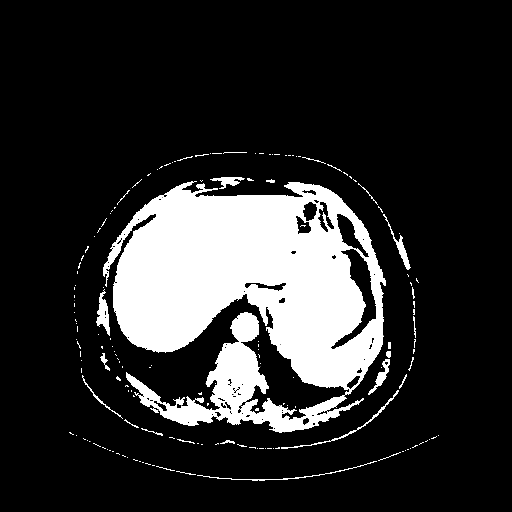

Generated VENOUS CT scan (A→B translation)

Full window (WL 1023.5, WW 4095 β†’ Low βˆ’1024, High +3071)

Actual HU range: [-1024.0, 3071.0]